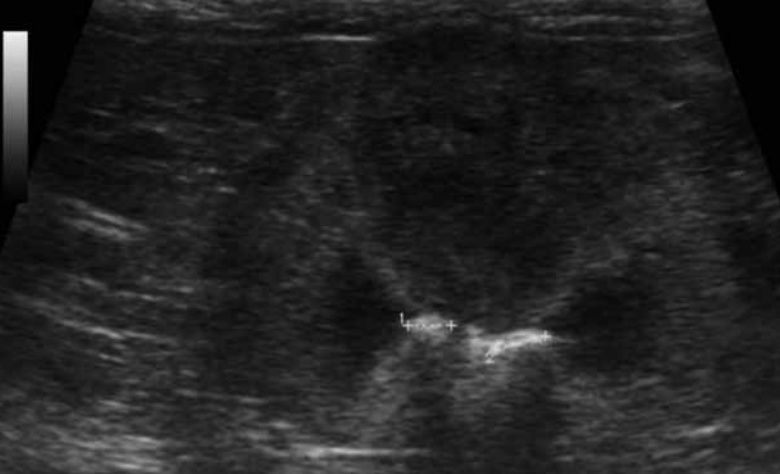

6-3. 신결석(Nephrolithiasis)(그림 14)

신결석은 강한 반사 표면과 원위부위의 음향 음영(그림자; acoustic shadowing)을 보입니다(이는 결석 크기 및 탐촉자 주파수에 따라 차이가 있을 수 있음). 위치는 신배, 신우, 근위 요관 등에서 나타나 보이며, 초음파 영상으로는 방사선 불투과성·투과성 결석 모두 탐지 가능하여, 이점에서는 방사선보다 장점이 될 수 있습니다. 폐색 동반 시 결석 근위부 액체 확장을 보입니다. 신우 내 액체에 둘러싸여 있거나, 명확히 신우 내에 위치하는 경우는 결석 진단 신뢰도가 높아집니다. 그리고 신실질의 석회화와 감별이 필요합니다.